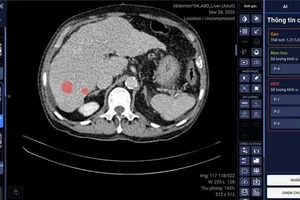

VinBrain cùng BV ĐH Y Dược TP.HCM phát hiện và chẩn đoán ung thư gan bằng AI

05/11/2022 15:53